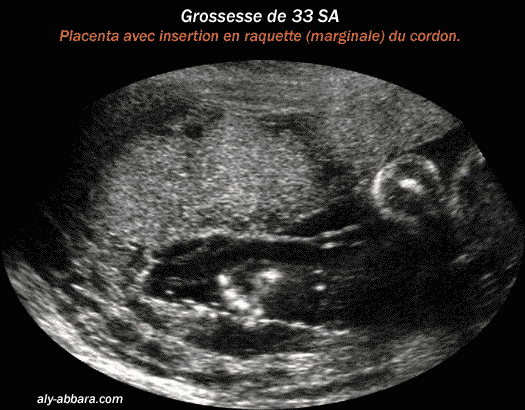

Placenta d'une grossesse à 33 semaines d'aménorrhée avec insertion marginale (ou en raquette)

du cordon ombilical sur la face placentaire ftale